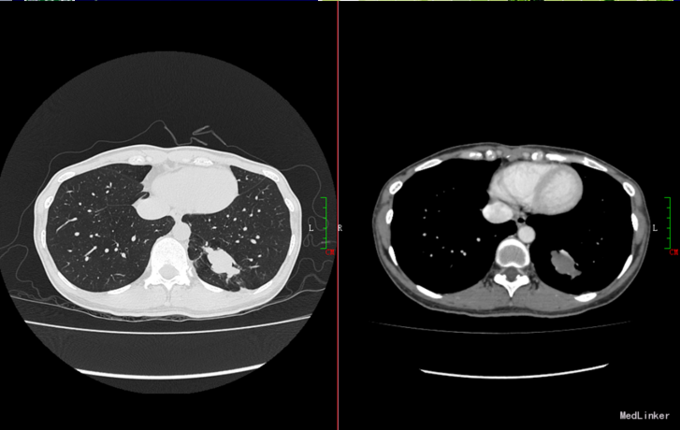

左肺下叶基底段

左肺下叶基底段,左肺下叶小结节

辅查:我院胸部ct示:左肺下叶后基底段结节,良性可能,建议进一步检查.

s7-8(左肺连在一起):它夹在中间,又往前走啊,不叫内前基底段,你告诉

s7:内基底段,s8:前基底段,s9:外基底段,s10:后基底段】 左肺 上叶【s1

看见左右主支气管(双眼)层面:右肺上叶前段和右肺下叶背段,左肺上叶和

两下叶支气管分出基底段时能观察中叶,舌叶及两肺下叶个基底段.